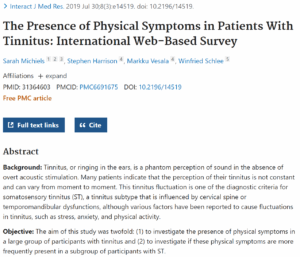

耳鳴りは非常に複雑な疾患であり、様々な方法で治療が行われています。耳鳴りを管理する多様な治療法がありますが、完治が検証された治療法はないのが現実です。イスチョク韓医院の頭蓋頸椎クリニックでは、耳鳴りの隠れた原因である頭蓋頸椎不安定性を中心的に扱っています。頭蓋頸椎不安定症がすべての耳鳴り疾患の原因となるわけではありませんが、一次的原因または関連要因である場合、頭蓋頸椎不安定症の治療は耳鳴りを緩和し、さらに寛解状態へ導くことができます。